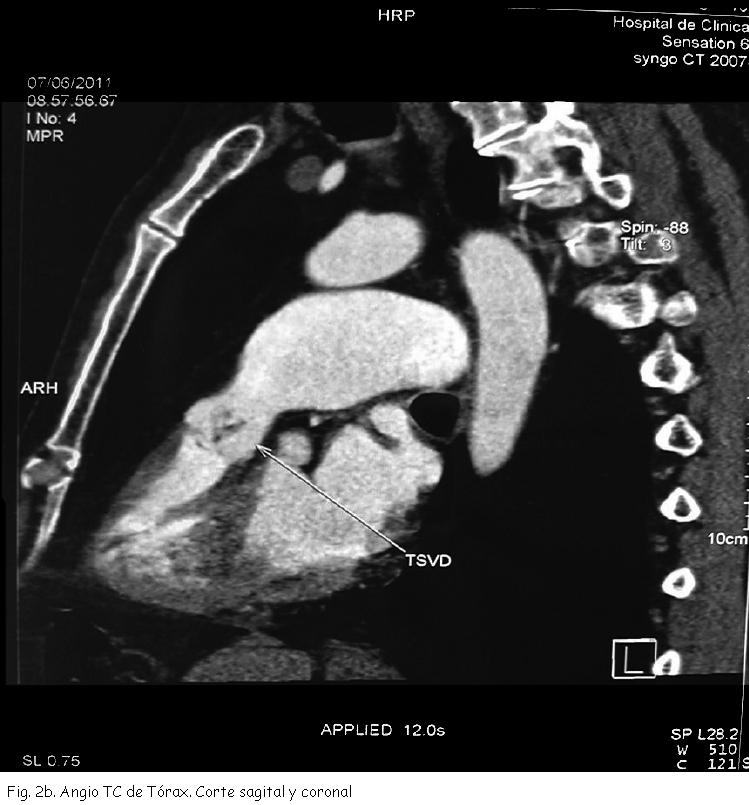

AngioTC y angioRNM de Tórax: dilatación aneurismática fusiforme de rama izquierda de arteria pulmonar de 42 mm de diámetro máximo que compromete toda su extensión (Figura 2 a, 2b).